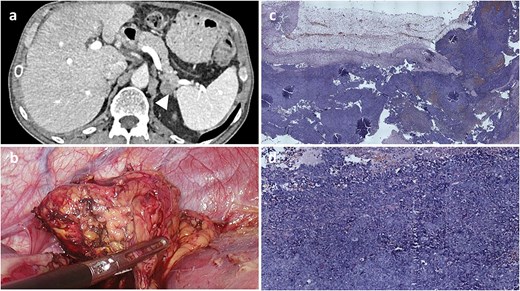

In June 2022, 13 months after surgery, abdominal CT detected a 20.5-mm mass in the left adrenal gland extending toward the pancreatic tail (Fig. 4). Following multidisciplinary team evaluation, the patient underwent a laparoscopic left adrenalectomy, lasting 45 min, with an estimated blood loss of 80 mL. The tumor was completely resected, and the patient recovered without postoperative complications.

Radiological, intraoperative, and histopathological findings of adrenal metastasis. (a) Computed tomography revealing a 20.5-mm mass in the left adrenal gland extending toward the pancreatic tail. (b) Intraoperative view of the adrenal mass. (c and d) Microscopic examination (H&E) showing malignant pigmented melanoma within adrenal gland tissue.

Microscopic examination revealed a tumor composed of epithelioid cells with heterotypic nuclei, nuclear grooves, folding nuclei, intranuclear inclusions, and multinucleation (Fig. 3c). Immunohistochemical staining was negative for inhibin, synaptophysin, cytokeratin-pan, and chromogranin A, while vimentin and melanocytic markers (S-100, human melanoma black-45) were strongly positive, confirming metastatic melanoma.

In January 2025, 20 months after recurrence follow-up CT imaging showed no evidence of disease progression.